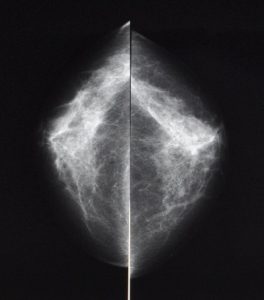

- Mamografie, mamograf

Jedná se o rentgenové vyšetření prsu za účelem odhalení počátku rakovinného bujení. Je základní zobrazovací metodou u většiny žen. Zpravidla se nehodí pro ženy mladé, u kterých je žláza bohatá a hutná. Mamografie se provádí na přístroji, mamografu, který využívá tzv. měkké rentgenové záření. Při vyšetření se prs musí dostatečně stlačit, je to nutné pro dosažení vysoké kvality snímku. Obvykle se vyšetřuje prs ve dvou rovinách, celkem se tedy provádí 4 snímky.

Některá mamografická vyšetření je nutno ještě doplnit ultrazvukovou kontrolou. Na našem pracovišti je toto vyšetření prováděno bezprostředně v týž den, v rámci jedné návštěvy pacientky. U plánovaného vyšetření je optimální vyšetřovat v první polovině menstruačního cyklu, kdy je možné prsy dostatečně stlačit bez nepříjemných pocitů vyšetřované ženy, při nebezpečí z prodlení (při podezření na zhoubný nádor ) se nečeká.Co je mamografický screening?

Přístrojové vybavení a ukázkové snímky:

- Mammomat Inspiration, Siemens